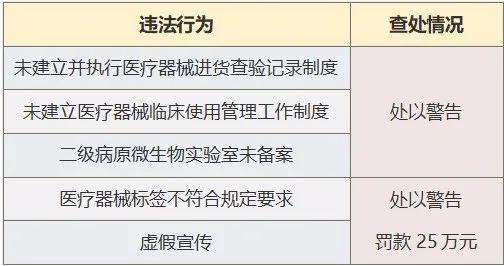

目前,相关部门已经介入调查。据最新消息,调查组已经对涉事医生进行了询问,并收集了相关证据。同时,调查组还对医院的医疗管理制度进行了审查,发现了一些问题。